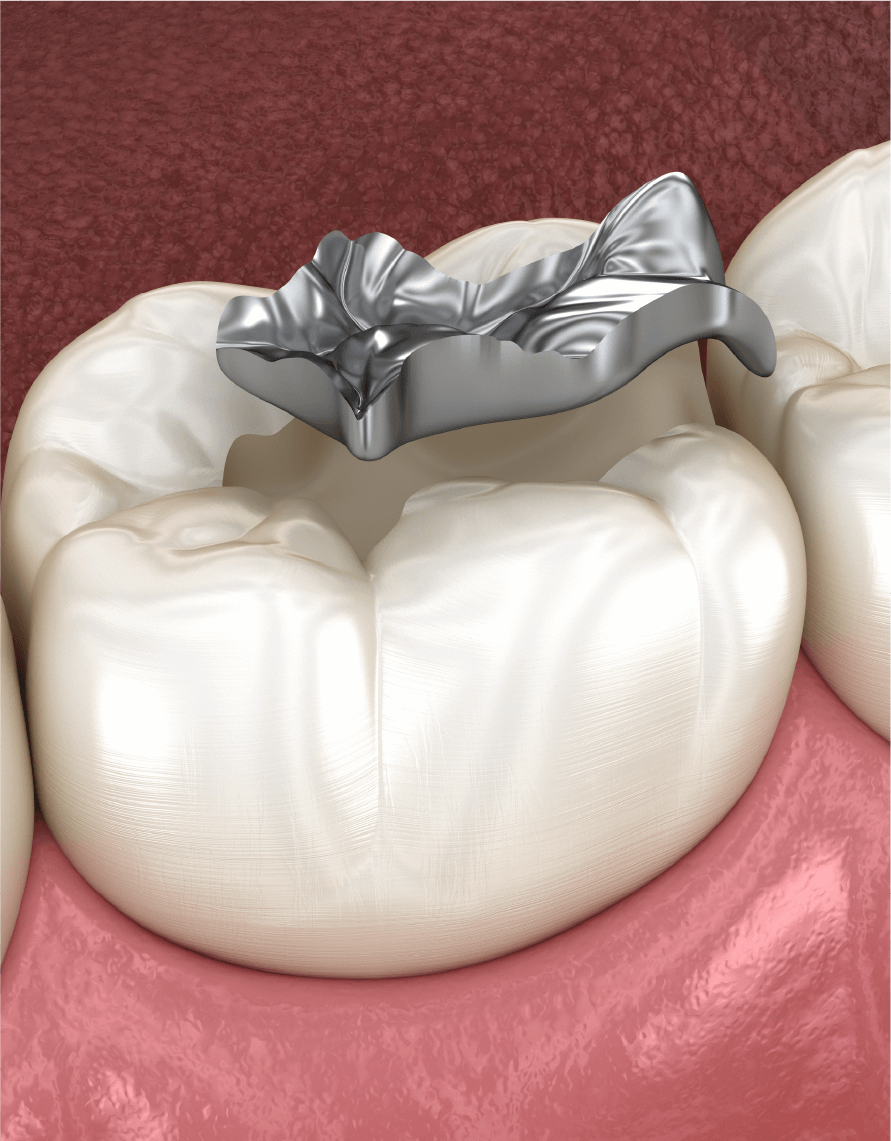

補綴治療

補綴治療詰め物・被せの提案と選定

歯を補強するインレー(詰め物)・クラウン(かぶせ)などの材質は、機能面・審美面・耐久面を考えて選びます。患者様の生活が長期的に過ごせるように、適切な詰め物や被せを選定し、必要箇所に、必要なだけ治療を行います。